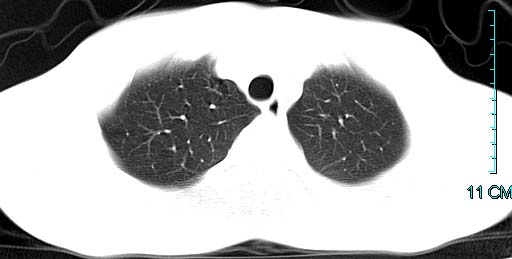

以下是引用ctkz987在2006-3-28 13:04:00的发言:[br]左侧胸腔积液穿刺后多发气液平(多房性),结合临床有高热不除外合并感染。

以下是引用qian在2006-3-28 14:32:00的发言:[br]左肺下叶大片状阴影,密度不均,见有条片影和空洞及气液平,少量胸腔积液伴有胸膜增厚,从图像看积液密度比水的密度高,结合病史,考虑左下肺化脓性炎症伴有脓胸。

以下是引用wawaquan在2006-3-28 22:25:00的发言:[br]左上肺舌段多发斑片影。结合“男24y咳嗽咳痰气促伴高热(38.5--39.5)20多天”及穿刺史,[br]考虑1 左下肺化脓性炎症;2脓胸。

以下是引用乡医在2006-3-28 18:37:00的发言:[br]左侧多发液气平面结合患者男24y咳嗽咳痰气促伴高热(38.5--39.5)20多天,查胸水:ldh239.3,总蛋白59.19,tb-ab阴性,利凡它试验+,红c2.7*109,白c1.08*109,分类淋巴92%分叶8%,考虑1脓胸2肺隔离征感染